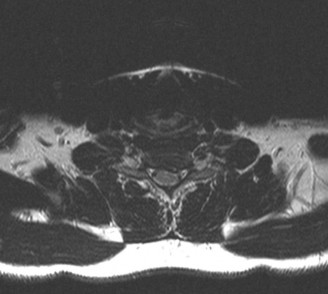

To evaluate the neural elements and the soft tissue structures, a comprehensive MRI of the lumbar spine without contrast was obtained. The T2-weighted sagittal and axial sequences confirmed the Grade 2 anterolisthesis and demonstrated severe bilateral foraminal stenosis at L5-S1. The exiting L5 nerve roots were severely compressed between the hypertrophied, fibrocartilaginous pseudarthrosis tissue of the pars defect dorsally, and the bulging, degenerated L5-S1 disc and superior endplate of S1 ventrally. Furthermore, the MRI revealed Modic Type II changes (fatty replacement of the subchondral bone marrow) in the adjacent vertebral endplates, confirming chronic biomechanical stress and discogenic degeneration. The central canal remained relatively patent, which is characteristic of isthmic spondylolisthesis, as the posterior neural arch is left behind during the anterior translation of the vertebral body.

Clinical & Radiographic Imaging Archive